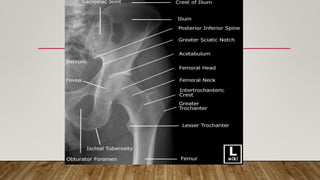

This document discusses radiology and the use of x-rays. It begins with an introduction to radiology and x-rays, noting their importance as the "father of medical investigations." It then discusses anatomy as seen on radiographs and whether x-rays are enough. The document goes on to compare gross views to radiological views, noting what each can and cannot show. It highlights important figures in the development of radiology, from x-rays to CT, MRI, and ultrasound. Specific anatomical structures visible on upper and lower limb x-rays are listed. The document concludes by discussing how pathologies appear on x-rays and the importance of clinical history and knowledge when interpreting radiological images.